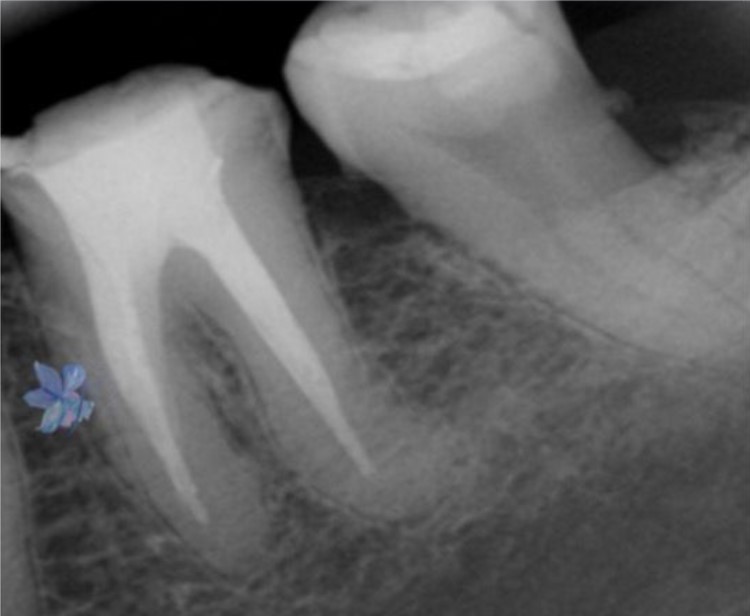

Casos Clínicos

Excelência comprovada em imagens radiográficas.

INICIAL

Diagnóstico Inicial

FINAL

Tratamento Concluído

Detalhes Radiográficos